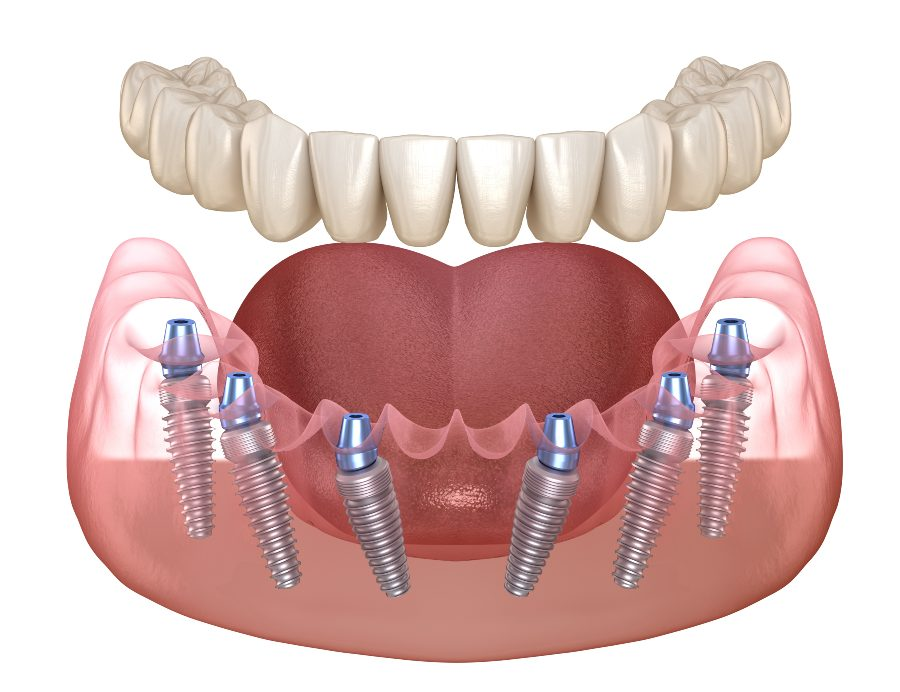

4 Implant Zest Fixed

- Complete Oral Evaluation

- Cone-Beam CT Scan

- All-Extractions If Needed

- 4 Implants per Arch

- Fixed Provisional PMMA Bridge

- Working with a team of experienced experts who can deliver a life-changing smile

Fixed Full Arch Dentures

- Complete Oral Evaluation

- Cone-Beam CT Scan

- All-Extractions If Needed

- 6 Implants per Arch

- Fixed Provisional and Final

- Working with a team of experienced experts who can deliver a life-changing smile

Permanent Zirconia Teeth Single Arch (all in)

- Complete Oral Evaluation

- Cone-Beam CT Scan

- All-Extractions If Needed

- 4 Implants per Arch

- Any needed bone graft

- Oral conscious sedation

- Fixed Permanent Single Arch Zirconia Teeth